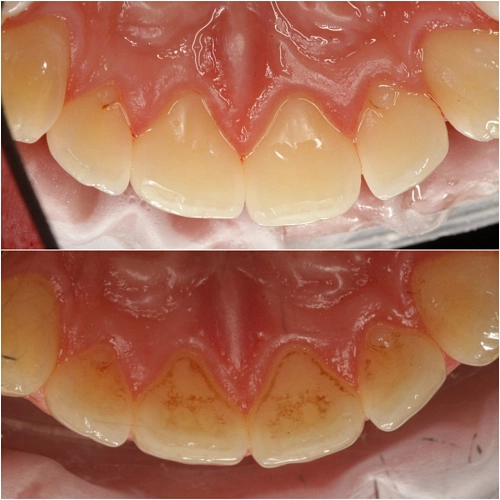

Почему любое лечение начинается с профгигиены?

В слюне и ротовой жидкости в среднем содержится больше 100 микроорганизмов в 1 миллилитре, а в зубном налёте — больше 1000 в 1 грамме. Во рту может одномоментно обитать 688 видов различных бактерий. Чтобы бактерии не попали в рабочую зону, ее при лечении изолируют стерильными салфетками и дезинфицируют, потому что в противном случае велик риск вторичного кариеса под пломбой. В процессе профгигиены мы удаляем  микробную пленку, которая образуется уже в течение двух часов после чистки зубов пастой. Если ее не убрать, то все эти микробы попадают под пломбу.

Также профгигиена необходима перед реставрацией. Доктору важно попасть в цвет,  так как налёт на зубах скрывает естественный оттенок.